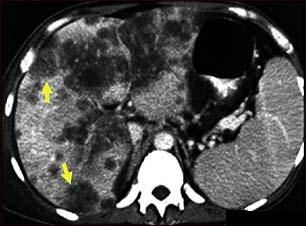

Screeningul cancerului hepatocelular